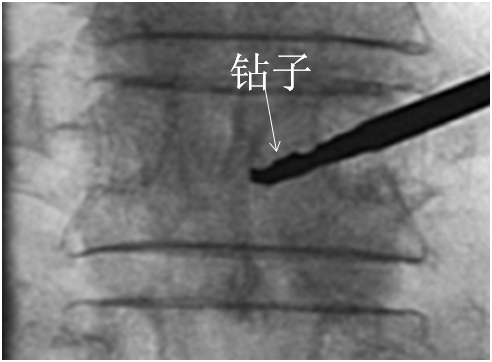

建立球囊通道

使用钻子开通道。

侧位相钻子直至椎体前中1/2交界处,正位钻头尖位于椎弓根影与棘突连线中点。

钻子必须出外鞘前端2cm,保证球囊完全进入椎体。

侧位像钻头尖在距椎体前缘2mm处停止正位显示钻头尖位于棘突边缘。